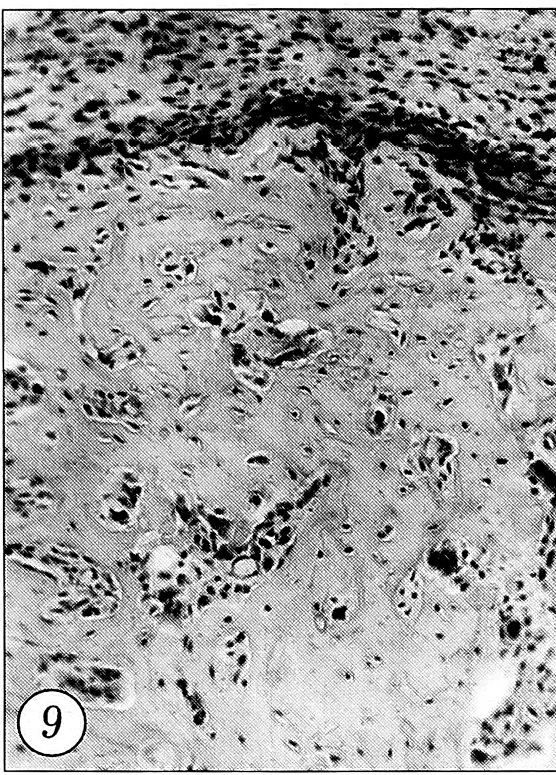

На 14-е сутки у животных основной группы формирование костной мозоли завершалось. Во вновь образованной кости отмечались морфологические признаки ремоделирования в виде появления многочисленных остеокластов (рис. 9). В мягких тканях, окружающих кость, доминирующими клетками становились молодые фибробласты.

Рис. 9. Многочисленные остеокласты вновь образованной кости, доминирование фибробластов в мягких тканях у ее поверхности. 14-е сутки после перелома при лазеротерапии (окраска гематоксилином и эозином, об. 10, ок. 10).